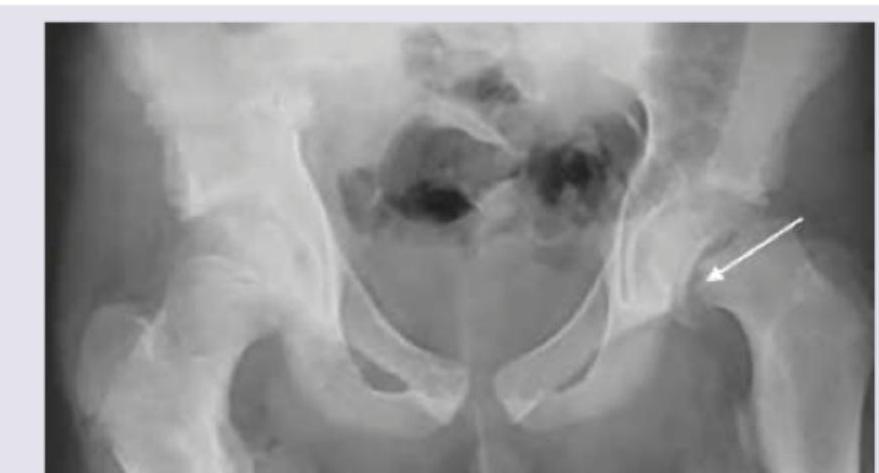

A 10-year-old obese boy has pain in the left groin after slipping during a basketball match 4 weeks back. On examination he has limitation of internal rotation. What does the given X-ray bilateral hip joint show?

Explanation: ***Slipped capital femoral epiphysis*** - The X-ray image (indicated by the arrow) shows **posterior and medial displacement of the capital femoral epiphysis** relative to the metaphysis, which is characteristic of SCFE. - The patient's age (10-year-old), obesity, groin pain, and **limitation of internal rotation** are classic clinical features of SCFE. *Developmental dysplasia of hip* - This condition involves abnormal development of the hip socket and femoral head, typically diagnosed in **infancy** or early childhood. - Radiographically, it presents as a **shallow acetabulum**, a small or abnormally positioned femoral head, and sometimes subluxation or dislocation, which are not seen here. *Septic arthritis* - Septic arthritis is an ** EMERGENCY** condition characterized by acute joint pain, swelling, warmth, and systemic signs of infection (fever, elevated inflammatory markers). - Radiographs may show **joint effusions** and eventually joint space narrowing and bone erosion, but not the specific epiphyseal displacement seen in the image. *TB hip joint* - **Tuberculosis of the hip joint** is a chronic infection that typically presents with gradual onset of pain, stiffness, and antalgic gait, often with systemic symptoms like weight loss and night sweats. - Radiographic features include **osteopenia**, joint space narrowing, and bony erosion, particularly in the weight-bearing areas, without the characteristic slip seen here.